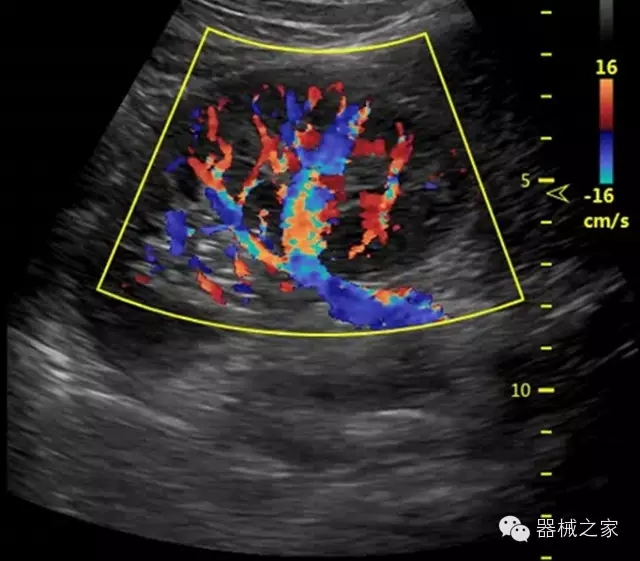

經(jīng)典產(chǎn)品:S8EXP

臨床圖片賞析

·智能微血流成像技術(shù):智能微血流捕捉技術(shù)可以提取出隱藏在背景噪聲中的弱血流信號(hào),大大提高低速血流的敏感性;

·移植S40高端臺(tái)式彩超高端平臺(tái)技術(shù),滿足超聲科腹部、淺表、婦產(chǎn)科、心血管、肌骨等應(yīng)用,提供超聲科完美解決方案;